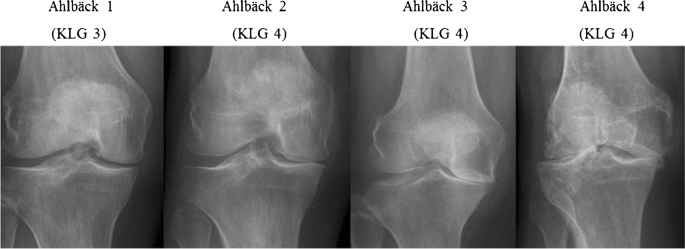

Kellgren-Lawrence derecelendirme sistemi: Bu sınıflandırma sistemi, röntgen bulgularına dayanarak diz osteoartritinin şiddetini değerlendirmek için yaygın olarak kullanılır. Durumu 0 ila 4 arasında derecelendirir ve daha yüksek dereceler daha ileri eklem dejenerasyonunu gösterir.

Ahlbäck sınıflandırması: Bu sınıflandırma sistemi özellikle diz eklemi osteoartritini değerlendirmek için kullanılır ve özellikle femoral kondil lezyonlarının varlığı ve derinliğine odaklanarak röntgen bulgularına dayanarak şiddeti değerlendirir.

OARSI sınıflandırması: Uluslararası Osteoartrit Araştırma Derneği (OARSI), diz osteoartritini semptomlara, fizik muayene bulgularına ve görüntüleme sonuçlarına göre farklı evrelere (0-4) ayırmak için hem klinik hem de radyografik kriterleri birleştiren bir sınıflandırma sistemi geliştirmiştir.

Bu sınıflandırmaların tedavi kararlarını yönlendirmeye yardımcı olmak ve diz artritini değerlendirmenin standart bir yolunu sağlamak için kullanıldığını unutmamak önemlidir. Tanı ve sınıflandırma, artrit durumlarını değerlendirme ve yönetme konusunda deneyimli bir sağlık uzmanı tarafından yapılmalıdır.

20. yüzyılda röntgen görüntülemenin ortaya çıkması, diz artritindeki eklem değişikliklerinin daha iyi görüntülenmesini sağladı. Bu da Kellgren-Lawrence derecelendirme sistemi gibi daha doğru tanı ve sınıflandırma sistemlerinin ortaya çıkmasını sağlamıştır.